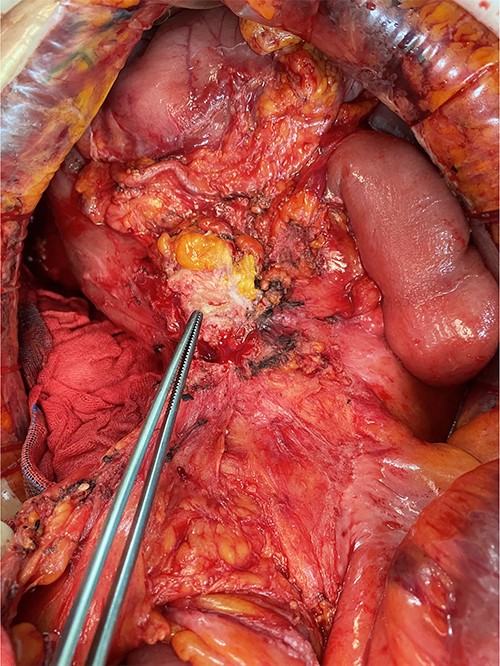

We made an incision avoiding the tumor. The patient’s abdominal cavity showed overall adhesion due to previous surgery. We found tumor invading or being adherent to the duodenum and superior mesenteric vein (Fig. 3). We thought that superior mesentery vein (SMV) collapsed due to compression, but it was identified completely occluded due to invasion. We also found that jejunal first branch was very dilated due to obstruction (Fig. 4). We performed completion right hemicolectomy with duodenal segmental resection, SMV resection and anastomosis (Fig. 5). Anterior resection was performed for the accompanying sigmoid colon cancer.

Dilated jejunal first branch of superior mesenteric vein (red arrow).